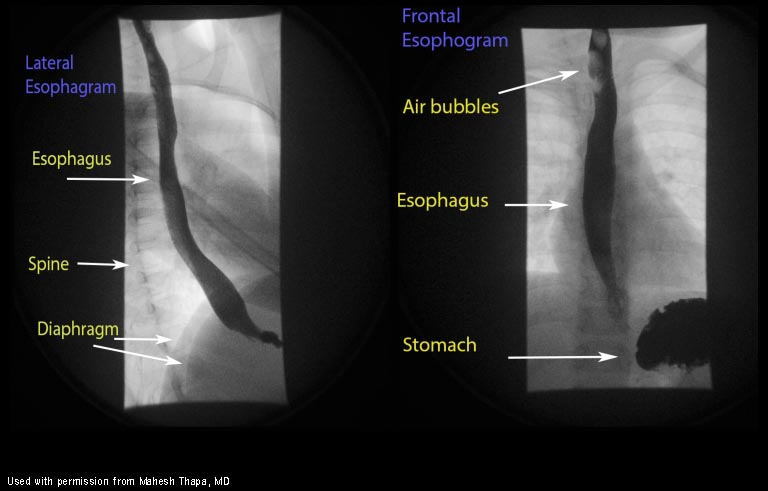

Results of a normal upper GI fluroscopy study

Results of upper GI fluoroscopy in a child with malrotation-volvulus

Corkscrew jejunum is also often seen